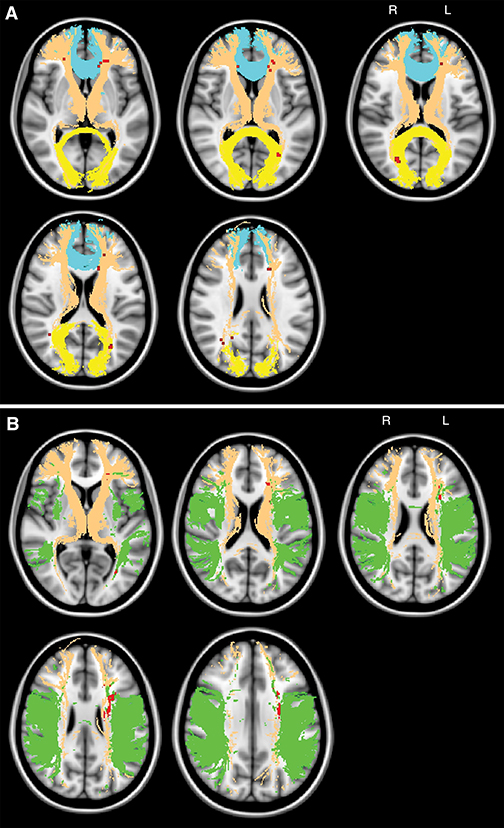

In a multimodal MR imaging study of 108 patients with symptomatic CAD but no dementia, Dewen Meng, MSc, of the University of Nottingham, England, and colleagues conducted comparisons and interrelations between global cognitive and fluency performance, lesion topography and ultrastructural damage, assessed with voxel-based statistics. Associations between cognition, medial temporal lobe atrophy lesion volumes, and global white matter ultrastructural damage indexed as increased mean diffusivity were tested with regression analysis by controlling for age.

In patients with CAD, researchers determined that cerebrovascular lesion location in the thalamic radiation and interhemispheric fiber tracts contributes to global cognitive deficits and lesions in the tha-lamic radiation and long association fibers affect fluency performance. Severity of subcortical tissue damage — preferentially in major white matter tracts — contributes to global cognitive impairment with skeleton mean diffusivity as the best-performing imaging marker for the prediction of probable vascular cognitive disorder, researchers determined.